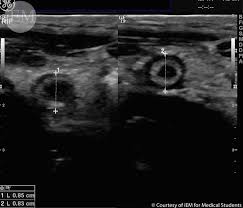

4. 복부 초음파: 복부 초음파 검사는 충수 부위의 염증 또는 다른 구조적인 이상을 확인하는 데 도움이 됩니다.